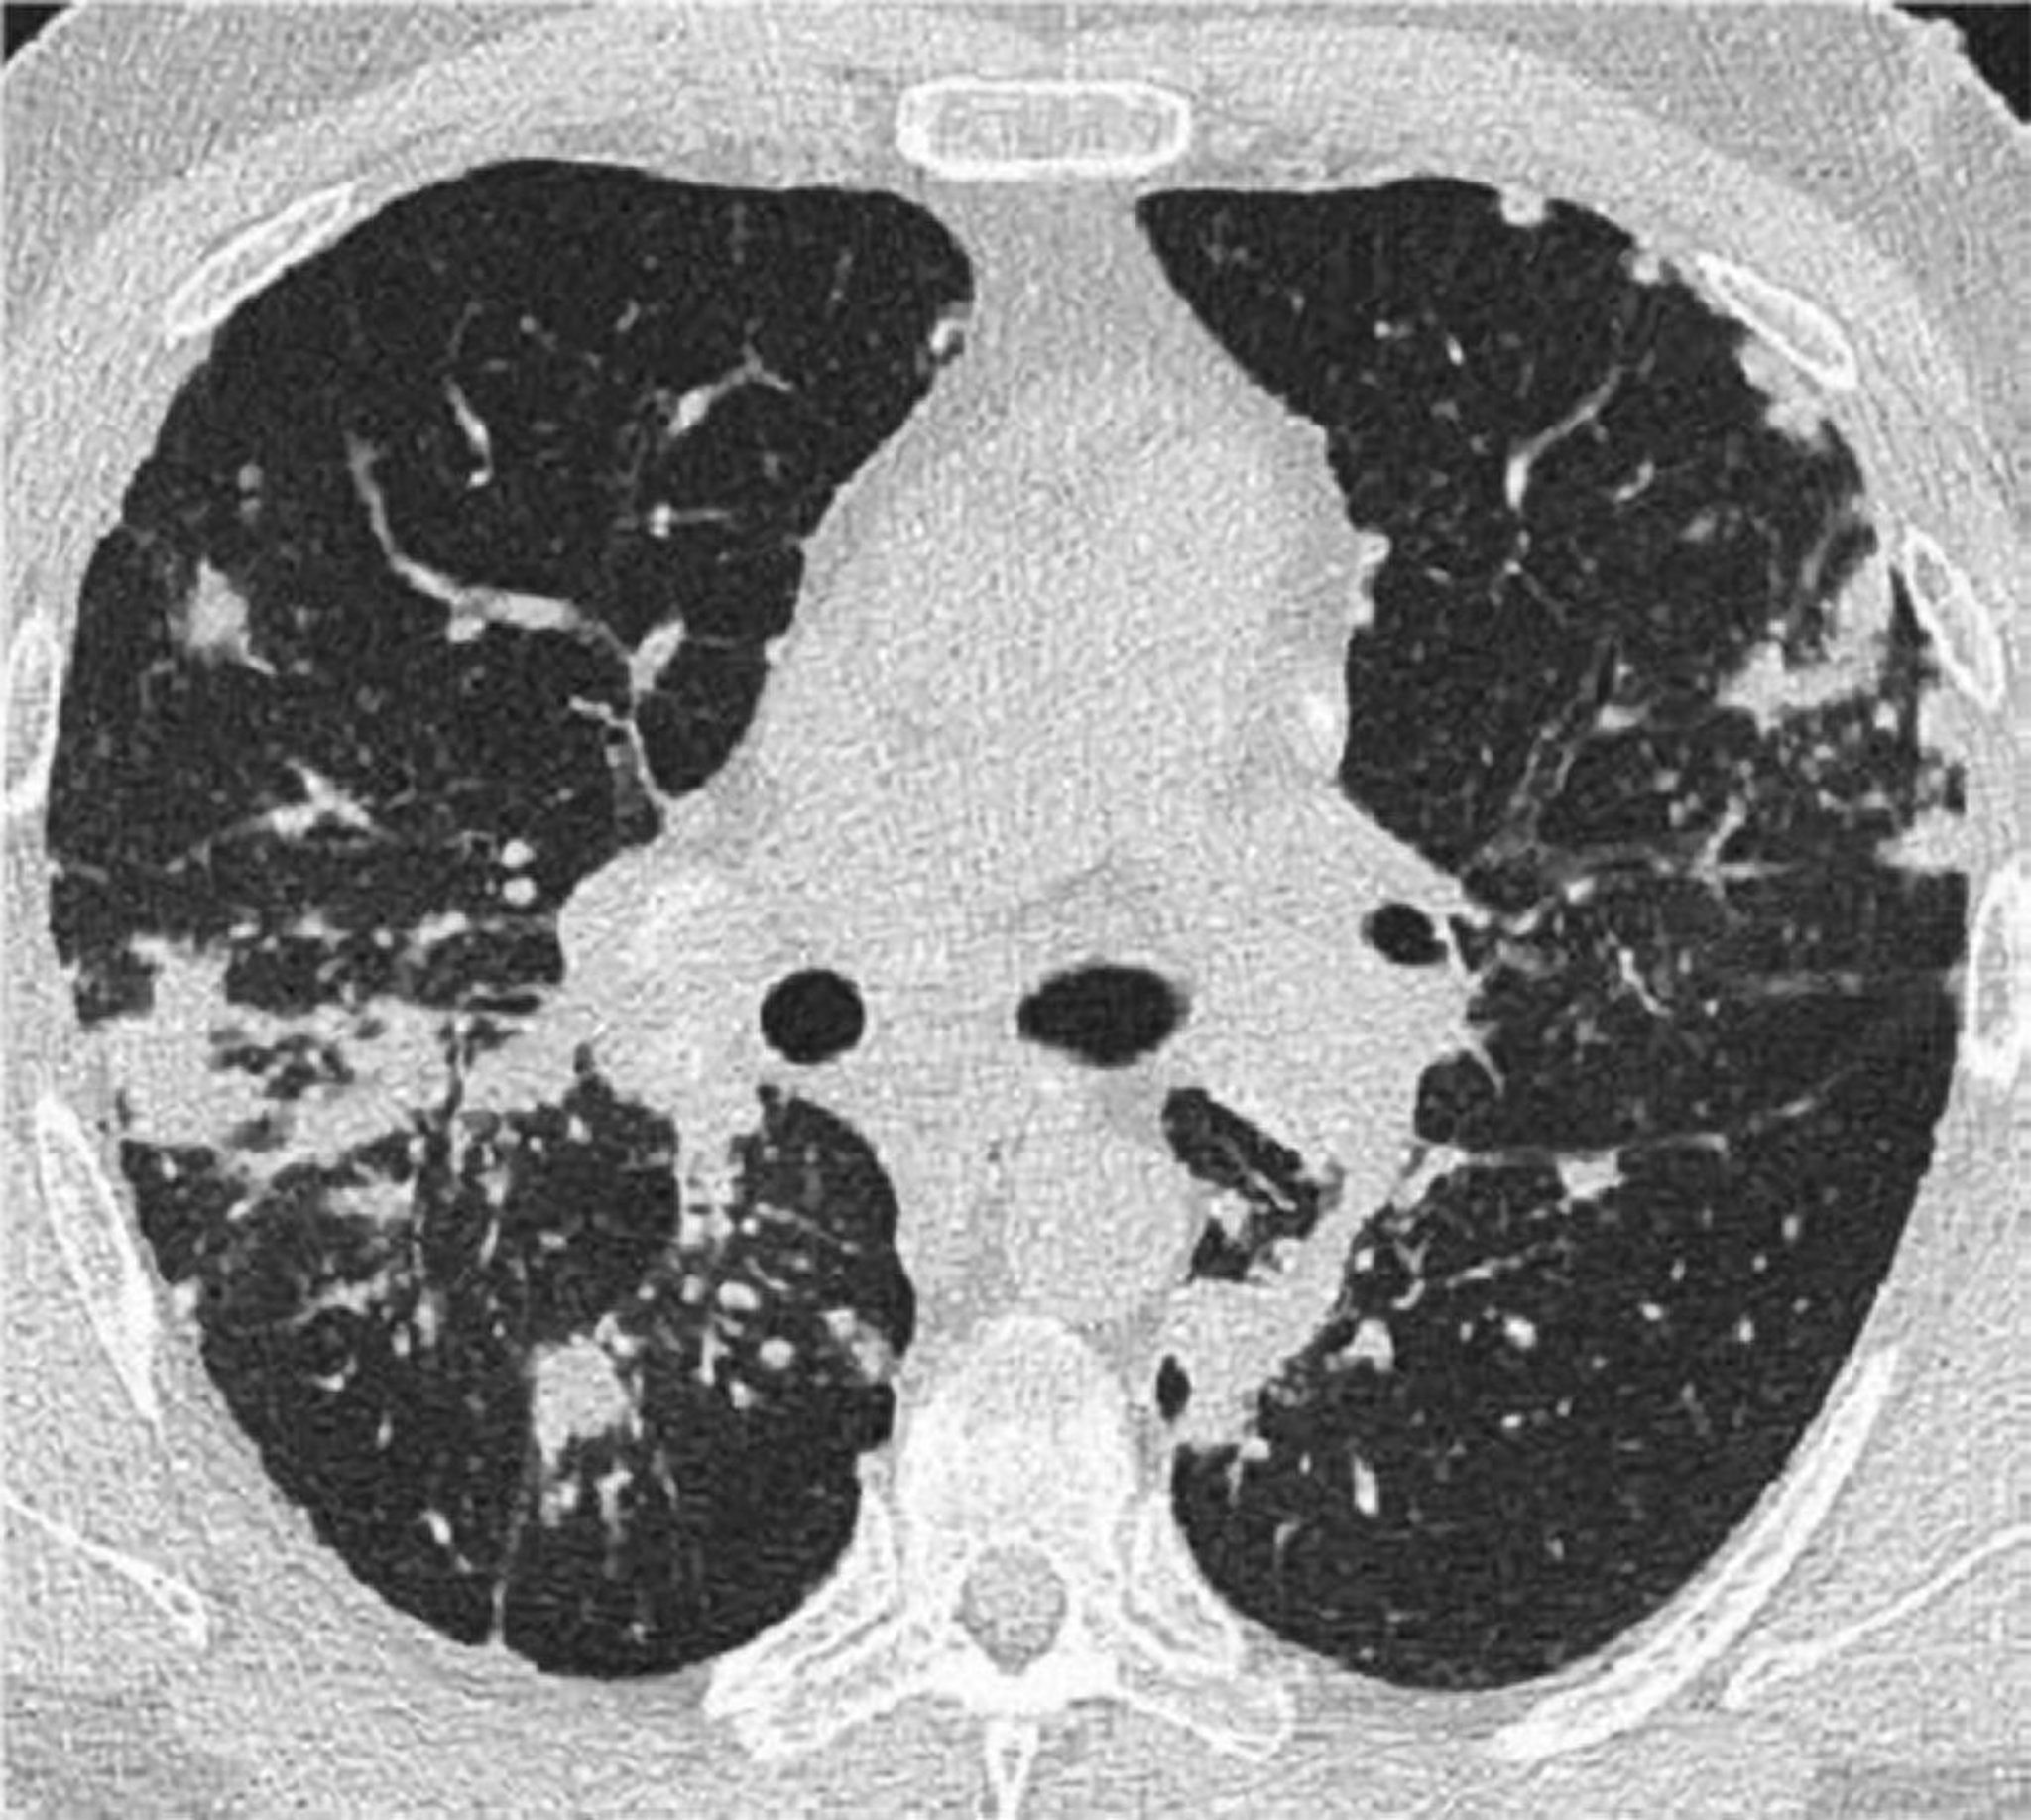

TC del torace nella sarcoidosi polmonare

Questa TC ad alta risoluzione del torace di un paziente con sarcoidosi polmonare mostra ispessimento dei fasci broncovascolari e perline dei setti interlobulari.

Image courtesy of Birendra P. Sah, MD, FCCP.